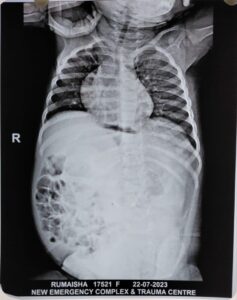

लखनऊ। प्रयागराज के बाद लखनऊ के KGMU में भी ‘फीटस इन फीटू’ का एक केस सामने आया है। यहां पीडियाट्रिक सर्जरी के विभागाध्यक्ष प्रो. जेडी रावत व उनकी टीम ने दुर्लभ सर्जरी कर 13 माह की बच्ची के पेट से बड़ी गांठ को निकाला है। गांठ में हड्डी एवं शरीर के अन्य भाग बाल, आंत भी विकसित हो गए थे। पिछले दिनों प्रयागराज में भी फीटस इन फीटू का मामला सामने आया था, वहां सात माह के शिशु की सर्जरी की गयी थी।

यही नहीं बच्ची कुछ खा पी भी नहीं पा रही थी, जिसकी वजह से उसका वजन भी लगातार कम हो रहा था। परेशान मां-बाप गंभीर हालत में बच्ची को लेकर लखनऊ स्थित KGMU ट्रॉमा सेंटर पहुंचे। उसके बाद यहां बच्ची को पीडियाट्रिक सर्जरी के प्रोफेसर जेडी रावत की टीम की निगरानी में भर्ती किया गया। जांच के बाद पता चला कि बच्ची के पेट में बड़ी सी गाँठ है जो बड़ी नसों, धमनियां, बाएं गुर्दे तथा बाएं फेफड़े की झिल्ली से चिपकी हुई थी।

प्रोफेसर जेडी रावत एवं उनकी टीम ने बच्ची का 31 जुलाई को ऑपरेशन किया। कैंसर की गाँठ को सफलता पूर्वक बड़ी नसों, धमनिया तथा बाएं गुर्दे को बचाते हुए निकाल दिया। जिसमें 3 घंटे का समय लगा। बच्चा वार्ड में अभी स्थिर हालत में है तथा स्वास्थ्य में सुधार हो रहा है।

इस बीमारी को फ़ीटस इन फिटु (Fetus in fetu) कहते हैं। क्योंकि इस गाँठ में हड्डी एवं शरीर के अन्य भाग बाल, आंत भी विकसित थे। यह एक विरल असाधारण बीमारी होती है। जो कि पांच लाख में से एक बच्चे में पायी जाती है।